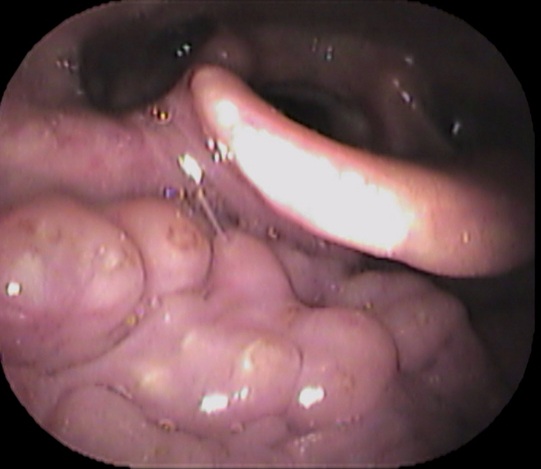

まずは喉を診てみます。

見える範囲には異常を認めませんでした。

続いてファイバーで奥をチェックします

声帯の一部に白い隆起がありました。

どれかと言いますと↓

赤丸部分です。

逆流性食道炎のアンケート結果が高値で、逆流性食道炎が原因の喉頭肉芽腫と診断しました。

喉頭肉芽腫とは、慢性的な刺激が原因で声帯の後方の粘膜が炎症を起こし、白く隆起する疾患です。

逆流性食道炎が原因で声帯後方の粘膜が白く隆起したと考えられます。

逆流性食道炎の治療薬で、白い隆起は縮小していきました。

「喉違和感」「詰まった感じ」がある方は、耳鼻咽喉科の受診をおススメいたします